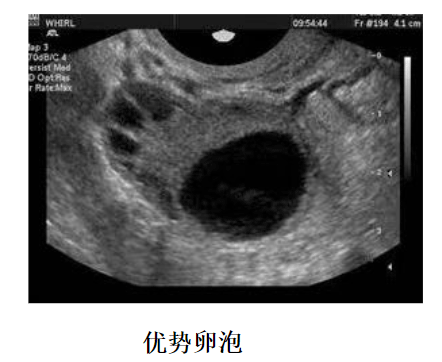

卵泡监测方法就是阴道B超检测,如果想要更加准确的判断卵泡发育程度、排卵日和黄体功能如何的话,建议配合基础体温检查,每次检查时间很短,不用担心花费太多时间。

2、时间把握,在月经周期较长的患者进行卵泡监测的时候,建议从月经周期第10天开始,如果期间有发现12mm以上的卵泡,则需要每天监测一次,如果并没有发现什么优势卵泡,可以3天监测一次。

A:如果卵泡监测到卵泡大小在12mm以下的时候,三天一次,当监测到卵泡大小为12mm以上的时候,建议一天监测一次,当卵泡趋近成熟的时候,可能需要一天监测两次,如果一直没有监测到卵泡,也是三天一次,后面根据卵泡数量进行跟进,一直监测到卵泡成熟为止。